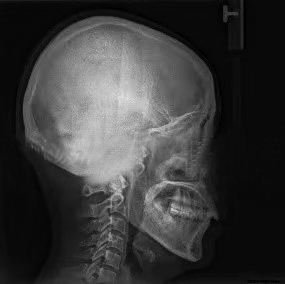

颞下颌关节由关节窝、髁突、关节盘及其周围软组织构成。髁突位于关节窝内,关节盘将髁突与关节窝分割为上下两个间隙,以避免骨性凹陷与髁突直接接触造成损伤。一般来说,髁突在关节窝中的矢状向位置关系更容易受到咬合闭合道及闭口位的影响,从而建立不良的关节结构关系,把关节盘挤出关节窝,造成髁突与关节窝之间的直接接触,损伤髁突。 髁突在关节窝中处于什么样的生理位置才有利于关节的功能运动及咬合,评价标准一直不统一。 近年来,更多的研究结果证实,在关节结构正常的条件下,牙尖交错位时的髁突在矢状向上基本处于居中的位置,即前后间隙甚至包括上间隙基本相等,这可以作为关节结构分析的参考。同时,牙尖交错位时,关节结构及其周围肌群甚至牙周状态均是协调舒适的,下颌运动时所有结构在这个过程中是轻便无障碍的。然而,这些理论均是建立在关节结构没有损伤的前提下,一旦结构发生损伤,比如髁突吸收,很难找到一个可量化的标准,理想的量化标准只能作为参考。 对于损伤后的关节,如何定位和评价其结构是否合理,目前没有相关概念和指标进行描述。理论上认为,颞下颌关节结构正常时,髁突在关节窝中的位置居中;已经损伤的髁突在关节窝中应有一定的修复空间,无论关节盘处于什么样的状态,只要在临床上患者没有任何不适且下颌功能正常,并经过一定时间的观察发现预后良好,就可以定义为关节舒适位。“舒适的”不一定全是形态健康完整的,损伤后的结构在舒服的环境中有可能慢慢修复;在不舒服的环境中,健康无从谈起。截至目前,还没有公认的关于关节结构,尤其是髁突位置和关节盘状态准确的、定论性的统一标准,也没有关于关节功能紊乱患者的治疗评价标准。

对咬合异常患者要进行临床检查、面型分析、影像学检查等,然后对结果进行综合分析。临床面诊是第一位的,不仅可以看到患者静态的一般情况、面部和咬合特征,还可以观察到患者包括肌位、牙位状况在内的咬合运动、语言、呼吸、发音等功能特征。动态观察一定不可忽略。 除此之外,基于功能运动的咬合分析,对关节病患者使用什么仪器和检查方法,要根据具体情况选择。比如,对下颌各种运动形式的各种检查,可以观察到下颌的运动状态及牙齿尖窝接触点的情况,用来分析咬合是否有碍关节结构和功能的敏感点。具体的方法包括观察法、手诊法、咬合纸检查、T-Scan(T-扫描)动态咬合力检查、髁突运动轨迹描记、头影测量、夜磨牙片、牙尖斜度测量、锥形束CT检查、MRI(磁共振)检查等。 需要注意的是,所有的测量方法都有侧重,医生可以根据实际需要选择一种或几种方法。 一般来说,应用单一的方法难以准确地发现问题;几种方法联合应用,相互印证,相互补充,能让医生更加全面地分析是否存在不足或不正确。但是,对于致力于咬合病治疗的专业人士,掌握头影测量、锥形束CT和MRI的检查方法、制取与分析很有必要,这些也是比较基本的技能;否则,很难做出一个完整、系统、科学的治疗方案。